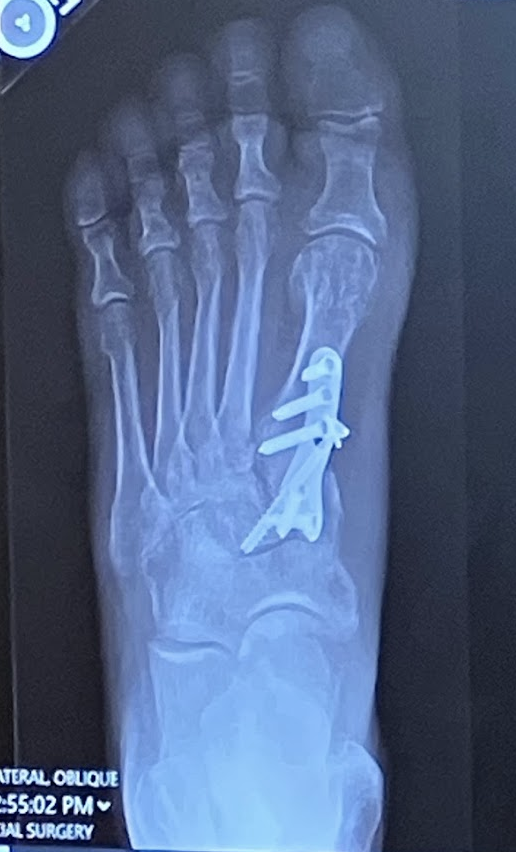

I had a severe bunion, which I tolerated for 20+ years. When I finally decided to have it corrected, I spent months researching orthopedic surgeons, procedures and outcomes. I found Dr. Ellis to be the absolute expert, most experienced and skilled surgeon based on his medical research and surgical experience. His practice is incredibly well run, responding to my questions with thorough responses, always same day. I traveled from Connecticut to New York for the procedure and follow-up, and it was truly worth the investment for what I deem the best possible outcome! I never imagined that 15 weeks later I would already be hiking and walking daily. Highly recommend Dr. Ellis, Stephen Costigliola and his practice!